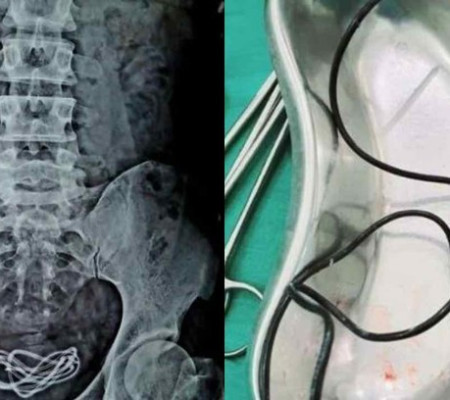

Um homem de 30 anos  inseriu  o cabo de um carregador de celular no próprio pênis . Afirmando estar com fortes dores abdominais, ele foi levado ao hospital, mas mentiu aos médicos que havia ingerido o cabo de quase dois metros de comprimento pela boca. O incidente bizarro aconteceu na Índia.

A mentira só foi descoberta na mesa de cirurgia, quando um exame de raio-X apontou o objeto na bexiga do indiano.

O médico que tratou o homem compartilhou a experiência sinistra no Facebook, mostrando o cabo sendo retirado com sucesso.